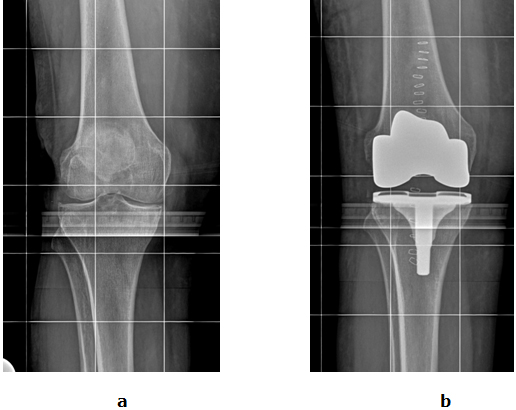

Abb. 2: a Arthrose des gesamten Kniegelenkes. b Die Oberfläche vom Inneren und Äußeren Gelenkanteil sind durch ein Kunstgelenk ersetzt (Oberflächenersatz).

Durch die Operation wird zudem die Beinachse begradigt und somit ein ausgeglichenes muskuläres Balancing erreicht.